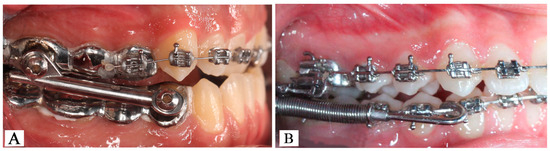

2.2. Orthopedic–Orthodontic Interventions